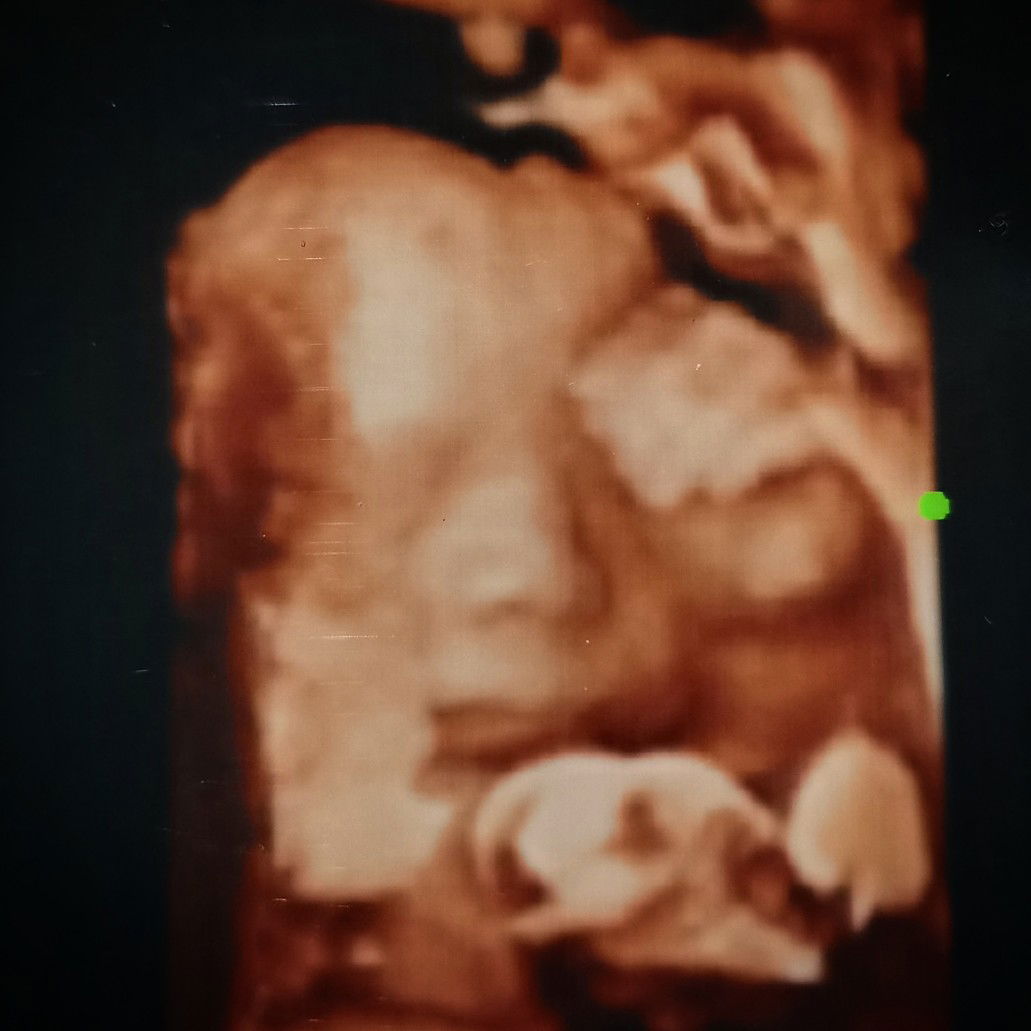

berat baby masa 28 weeks

Mummy's yg tgh pregnant skrg 28weeks. Berat baby brp ye?